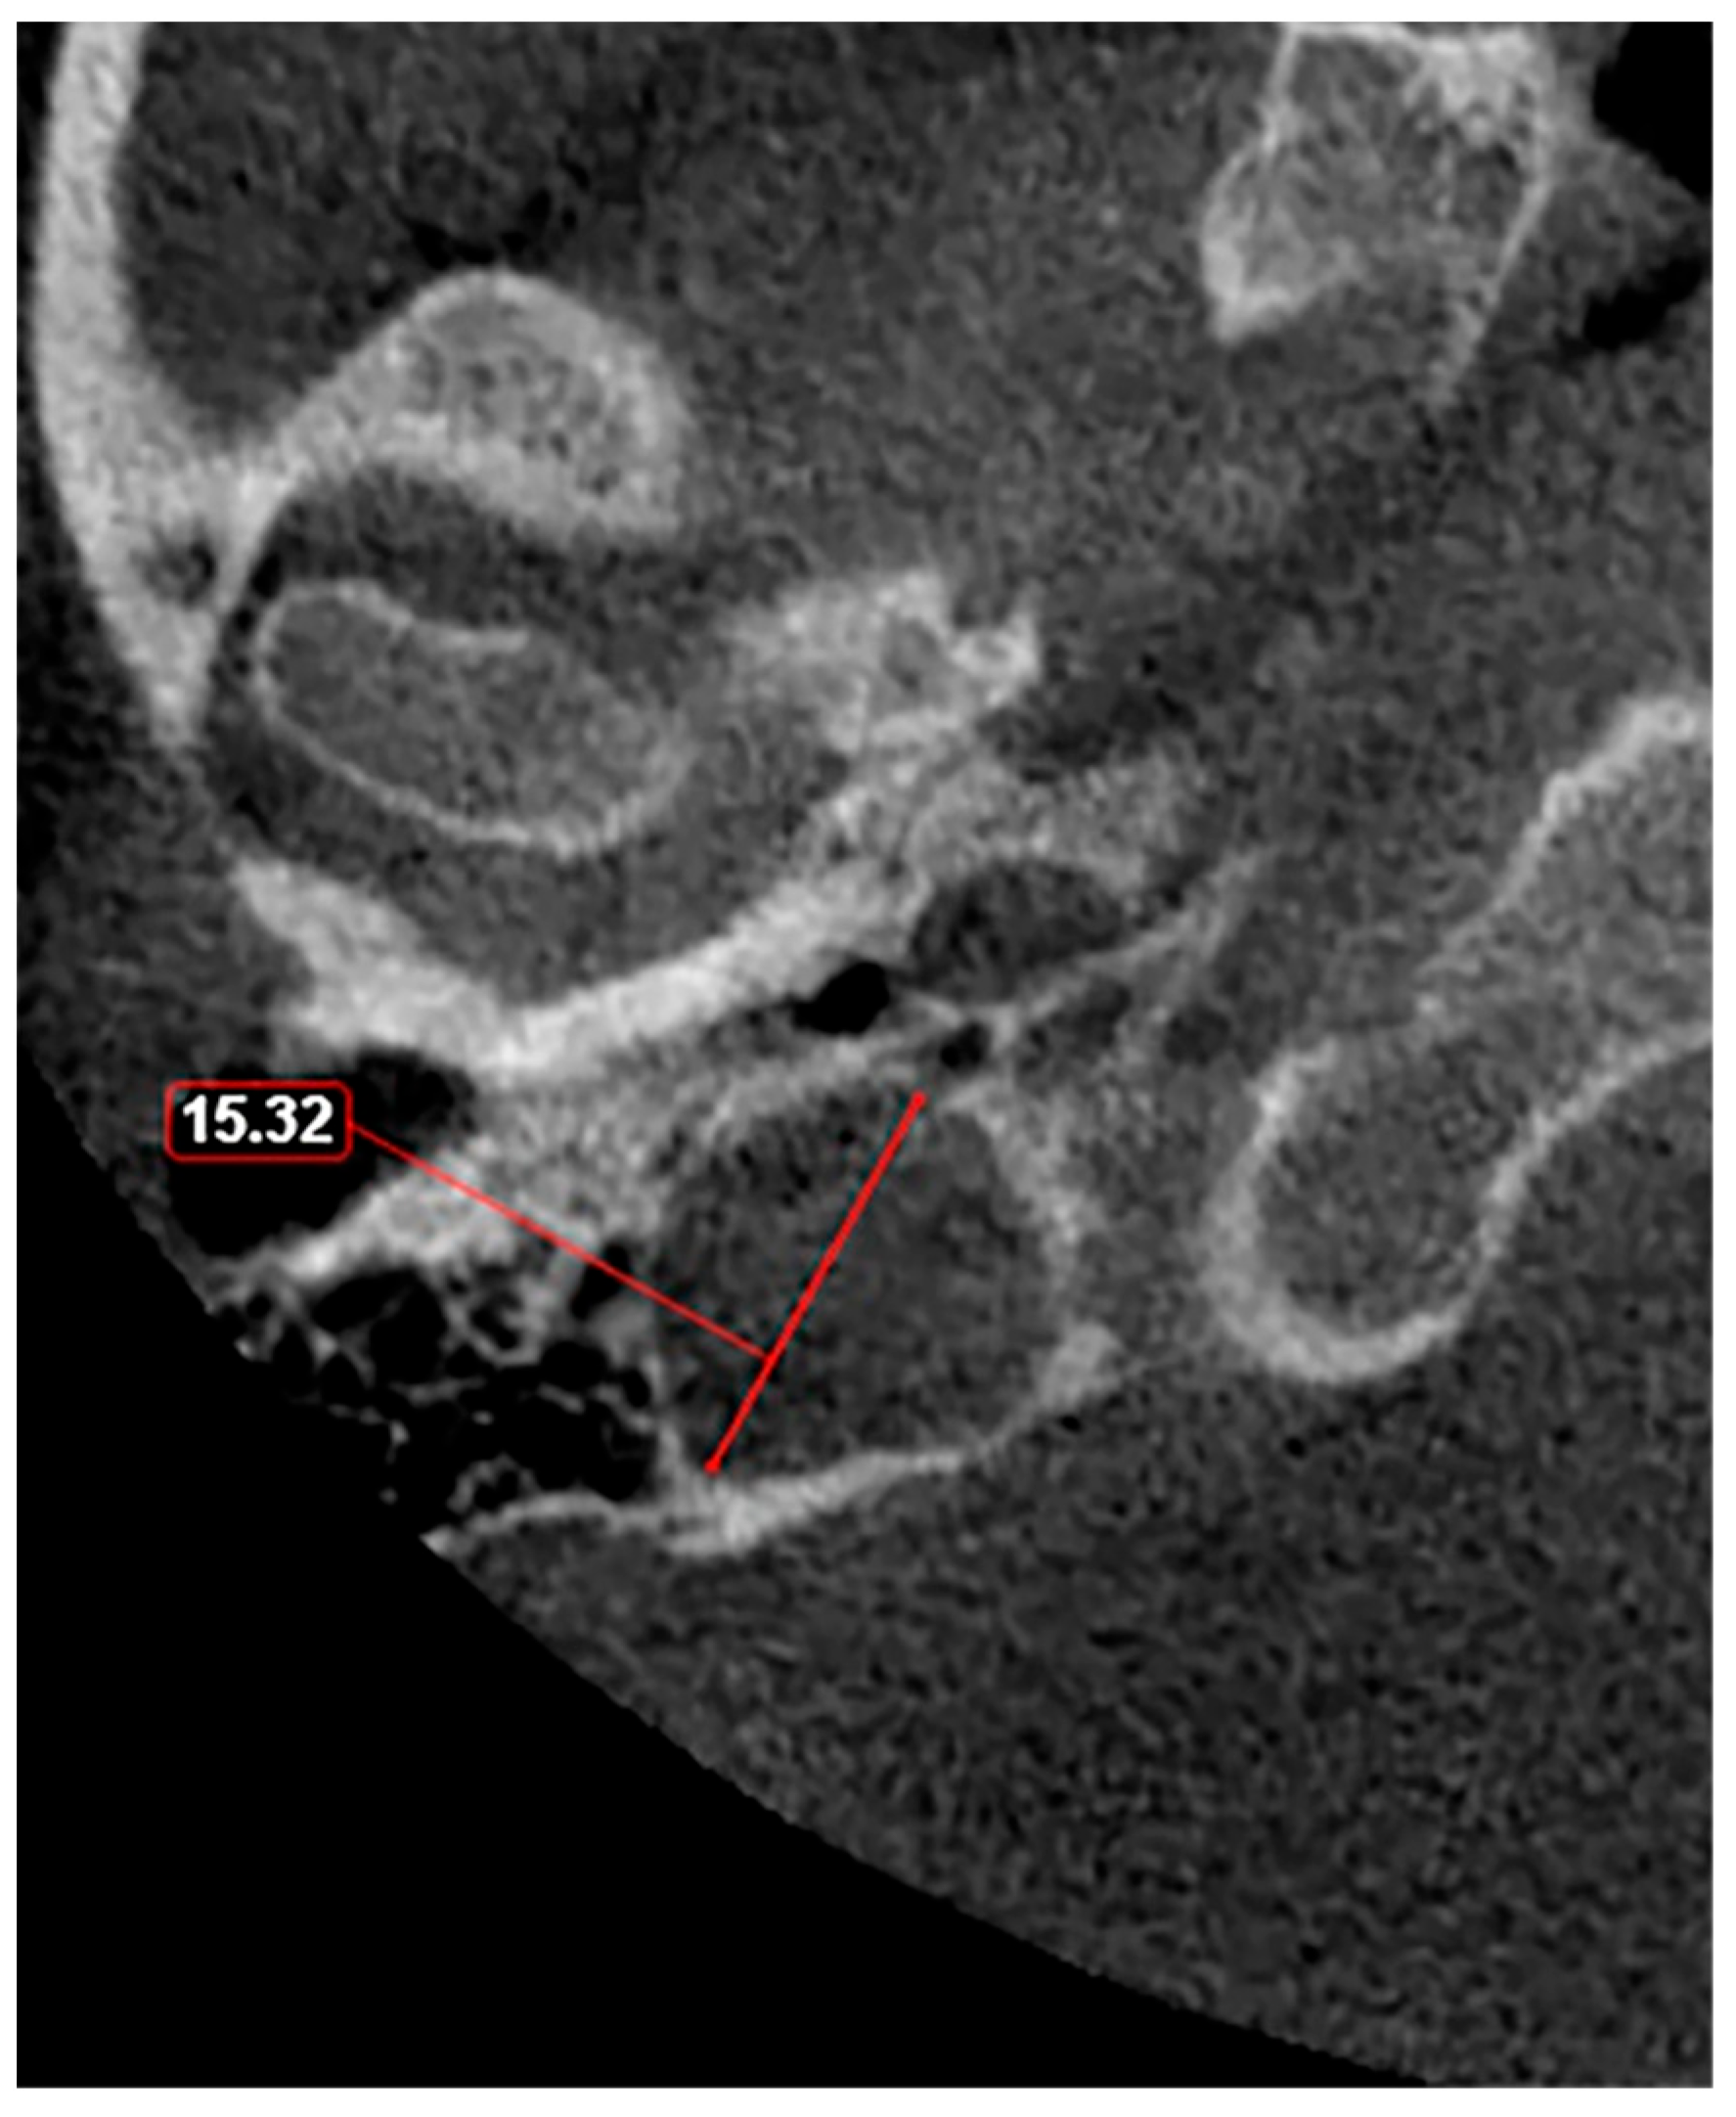

| Vachata et al. [14] | The apex of JB reaches/traverses the floor of IAC | Cadavers/HRCT | 15 |

| Roche et al. [49] | JB dome less than 6.5 mm below IAC | CT | 25 |

| Friedmann et al. [21] | JB rising above the level of the IAC in axial section | CT scans/Temporal bone histopathology | 8.5/8.2 |